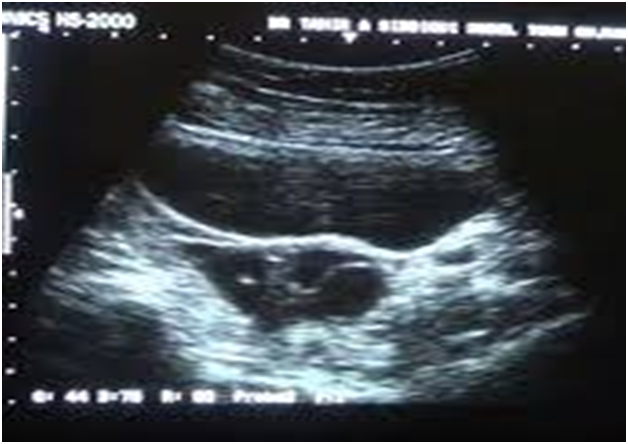

An 18 year old, unmarried girl presented to the emergency department with chief complaints of dull aching pain in the right iliac fossa since one day. The pain was waxing and waning in nature associated with a few episodes of acute exacerbations in the last 24 hours. Patient also had 2-3 episodes of non- bilious vomiting and constipation. Past history revealed that she was a known case of polycystic ovarian disease and had a similar episode of acute abdomen 5 months back which was conservatively managed and she was advised a 3 month course of oral contraceptive pill. Previous ultrasounds showed a persisting follicular cyst of around 5 cm in the right ovary along with bilaterally enlarged ovaries with peripherally arranged multiple small follicles. Patient had oligomenorrhoeic cycles and rest of the medical and surgical history was not significant. There was no history of fever, loss of appetite, vaginal discharge or urinary symptoms. Abdominal examination did not reveal any mass in the right iliac fossa but rebound tenderness was present. Blood investigations were sent along with CA-125 which were all found to be normal. Transabdominal scan revealed an enlarged right ovary with a clear cyst of 71x57x65mm along with a thick wall. Left ovary was also enlarged with peripherally arranged follicles and a simple cyst of 28mm. Colour Doppler revealed normal blood flow in both the ovarian vascular pedicles. Since the patient was a known case of PCOD, presence of enlarged ovaries with a persistent follicular cyst and normal blood flow, only made the diagnosis of torsion more challenging. But, considering the recurrent episodes of acute exacerbation, vomiting and persistent dull aching pain, authors decided to go for a diagnostic laparoscopic evaluation in order to rule out ovarian torsion.

Figure 2 Ultrasonography revealed a simple ovarian cyst of size 6 X 6 cm with intact blood supply in the pedicle.